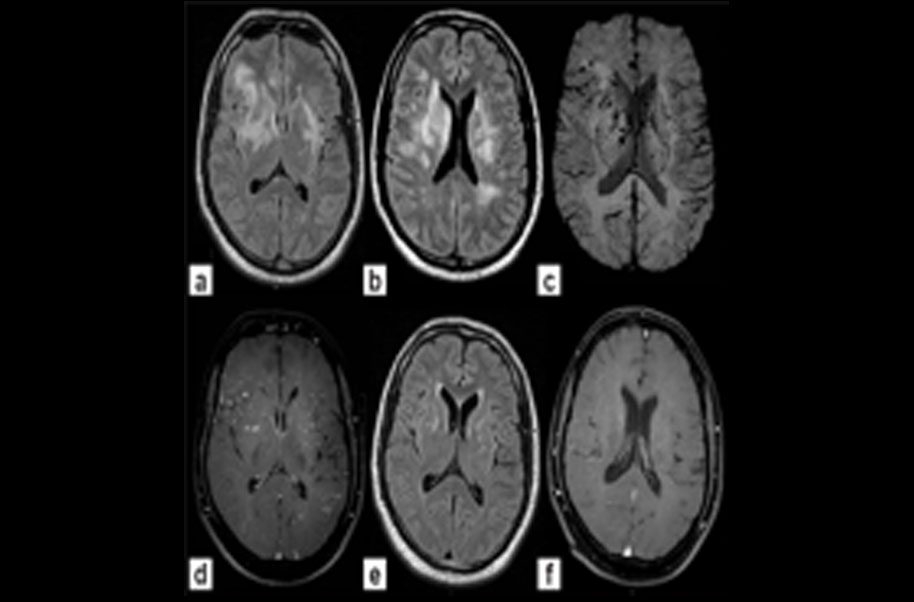

Subcortical Leukoencephalopathy

Binswanger's disease, also known as subcortical leukoencephalopathy, is a form of small vessel vascular dementia caused by damage to the white brain matter. White matter atrophy can be caused by many circumstances including chronic hypertension as well as old age.

Binswanger disease is primarily caused by atherosclerosis, thromboembolism and disorders in the blood vessels that supply the deep tissues of the brain. Other predisposing risk factors of binswanger’s disease include elevated cholesterol levels, heart disorders, diabetes, elevated blood pressure and history of smoking. Certain rare hereditary diseases such as cerebral autosomal dominant arteriopathy with subcortical infarcts and leukoencephalopathy (cadasil) may also lead to binswanger’s disease. Binswanger’s disease is not a specific disease. It is a clinical syndrome of a vascular dementia with multiple causes.